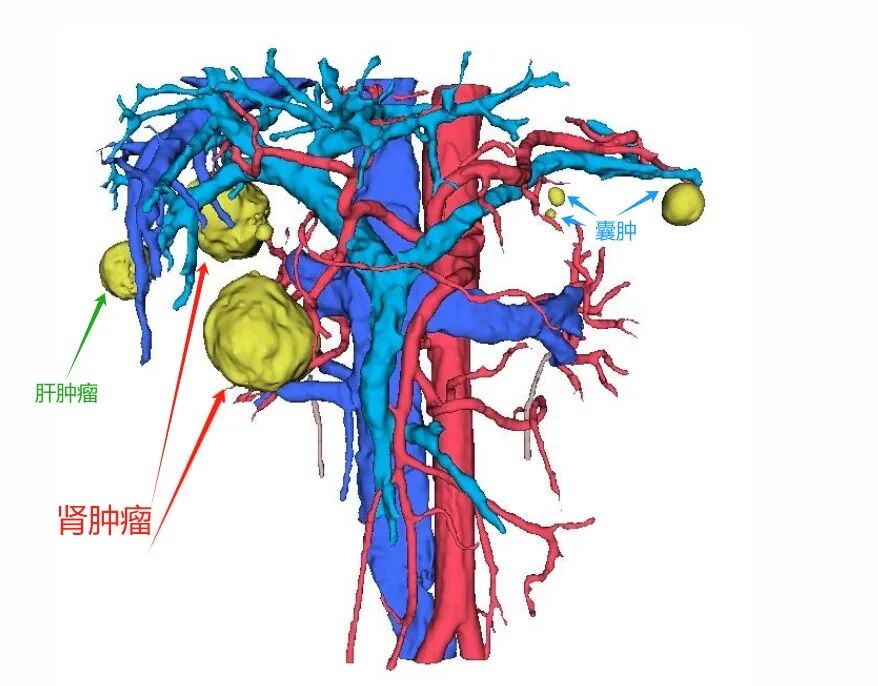

基本信息:患者右肾见约39*36mm肿瘤,考虑肾癌可能;两肾多发囊肿,左肾上腺内侧支结节,考虑腺瘤可能。

患者肾肿瘤切除手术的难度:主要在于肿瘤生长在肾窦内,靠近肾门部,位于最复杂的肾脏核心区域,周围被肾脏动静脉及集合系统包绕,任何周围组织的损伤很有可能造成手术失败,并且肾门部背侧肾脏正常组织较少,缝合难度大,术后易出现出血、漏尿等并发症。术前运用阿梵D三维重建技术详细评估肿瘤与肾脏各分支血管的解剖关系,全方位评估手术风险。

术前阿梵D——泌尿系统三维重建结果

CT扫描中,识别出7个病灶

其中最大肾肿瘤(约39*36mm)

三维重建中病灶位置信息